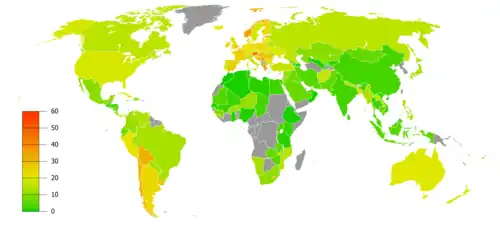

German scientists identified a link between smoking and lung cancer in the late 1920s, leading to the first anti-smoking campaign in modern history, albeit one truncated by the collapse of Nazi Germany at the end of World War II.[10] In 1950, British researchers demonstrated a clear relationship between smoking and cancer.[11] Evidence continued to mount in the 1960s, which prompted political action against the practice. Rates of consumption since 1965 in the developed world have either peaked or declined.[12] However, they continue to climb in the developing world.[13] As of 2008 to 2010, tobacco is used by about 49% of men and 11% of women aged 15 or older in fourteen low-income and middle-income countries (Bangladesh, Brazil, China, Egypt, India, Mexico, Philippines, Russia, Thailand, Turkey, Ukraine, Uruguay, and Vietnam), with about 80% of this usage in the form of smoking.[14] The gender gap tends to be less pronounced in lower age groups.[15][16] According to the World Health Organization, 8 million annual deaths are caused by tobacco smoking.[17]

From 1965 to 2006, rates of smoking in the United States declined from 42% to 20.8%.[12] The majority of those who quit were professional, affluent men. Although the per-capita number of smokers decreased, the average number of cigarettes consumed per person per day increased from 22 in 1954 to 30 in 1978. This paradoxical event suggests that those who quit smoking smoked less, while those who continued to smoke moved to smoke more light cigarettes.[45] The trend has been paralleled by many industrialized nations as rates have either leveled-off or declined. In the developing world, however, tobacco consumption continued to rise at 3.4% in 2002.[13] In Africa, smoking is in most areas considered to be modern, and many of the strong adverse opinions that prevail in the West receive much less attention.[46] In 2008, Russia (70.2%), Indonesia (65.3%), Belarus (63.6%), Ukraine (63.3%), Laos (62.5%), Greece (62.4%), Jordan (61.7%), Tonga (61.1%), China (60.8%), and North Korea (59.5%) were ranked the first by adjusted prevalence estimate of the percent of male population smoking tobacco.[47]

Smoking may be up to five times more prevalent among men than women in some communities,[61] although the gender gap usually declines with younger age.[15][16] In some developed countries smoking rates for men have peaked and begun to decline, while for women they continue to climb.[62]

The World Health Organization (WHO) states that "Much of the disease burden and premature mortality attributable to tobacco use disproportionately affect the poor". Of the 1.22 billion smokers, 1 billion of them live in developing or transitional economies. Smoking rates have leveled off or declined in the developed world.[64] In the developing world, however, tobacco consumption is rising by 3.4% per year as of 2002.[13]

The WHO in 2004 projected 58.8 million deaths to occur globally,[65] from which 5.4 million are tobacco-attributed,[66] and 4.9 million as of 2007.[67] As of 2002, 70% of the deaths are in developing countries.[67] As of 2017, smoking causes one in ten deaths worldwide, with half of those deaths in the US, China, India and Russia.[68]

Rates of smoking have generally leveled off or declined in the developed world. Smoking rates in the United States have dropped by half from 1965 to 2006, from 42% to 20.8% in adults.[122] In the developing world, tobacco consumption is rising by 3.4% per year.[123]